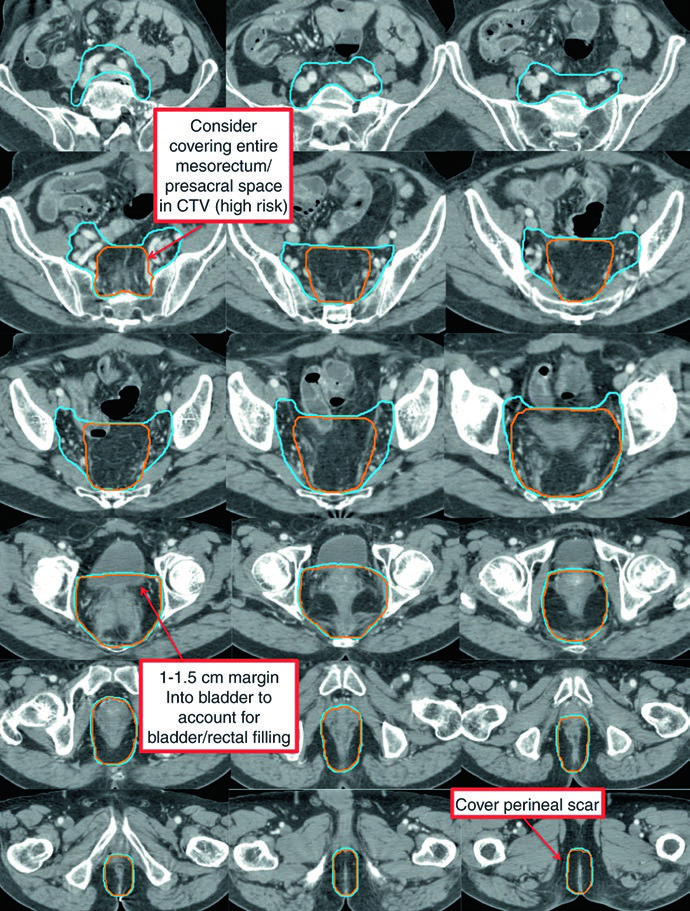

O CTV de alto risco (CTV-HR) deve incluir o GTV com margem mínima de 1,5 a 2 cm superior e inferiormente, além de todo o reto, mesorreto e espaço pré-sacral. Para linfonodos ilíacos externos ou inguinais macroscopicamente comprometidos, a margem GTV-para-CTV deve ser de no mínimo 10 a 15 mm. Em tumores T4, adiciona-se margem de 1 a 2 cm nos órgãos adjacentes invadidos (bexiga, próstata, cérvix).

O CTV de risco padrão (CTV-SR) cobre o CTV-HR completo, todo o mesorreto e os linfonodos ilíacos internos bilaterais. A inclusão dos linfonodos ilíacos externos e obturadores bilaterais é obrigatória para tumores T4 com envolvimento de órgãos anteriores (bexiga, cérvix, próstata). Se o tumor primário se estende inferiormente para o canal anal, os linfonodos ilíacos externos e inguinais bilaterais devem ser incorporados ao CTV-SR.

| CTV-SR | CTV-HR + mesorreto completo + linfonodos ilíacos internos bilaterais. Ilíacos externos e obturadores para T4 com invasão anterior. Inguinais para tumores com extensão para o canal anal. Superior: interespaço L5/S1 ou 2 cm acima da doença macroscópica. Inferior: assoalho pélvico ou 2 cm abaixo da doença. Margem de 0,7 cm ao redor dos vasos ilíacos internos. Margem anterior de 1-1,5 cm na bexiga |

No cenário pós-operatório, o delineamento segue princípios semelhantes ao pré-operatório. Após ressecção abdominoperineal (APR), todo o leito cirúrgico — incluindo a cicatriz perineal — deve ser incluído. Para doença residual macroscópica ou margem positiva, o CTV-P recebe margem de 1 a 2 cm excluindo osso, músculo e ar não envolvidos. O CTV-HR pós-operatório cobre o reto remanescente (se aplicável), o leito mesorretal e o espaço pré-sacral.

| Pelve inferior | Inferior: 2 cm abaixo da doença macroscópica, incluindo todo o mesorreto até o assoalho pélvico. Lateral: poucos mm além dos músculos levantadores, exceto se há extensão tumoral para a fossa isquiorretal. Margem de 1-2 cm para áreas de invasão em tumores T4 |

| Pelve média | Inclui reto, mesorreto, região dos ilíacos internos e 1 cm de margem na bexiga. Posterolateral até musculatura ou osso da parede pélvica. Anterior: pelo menos 1 cm na bexiga posterior. Margem de 7-8 mm em tecido mole ao redor dos vasos ilíacos internos |

| Pelve superior | Superior (perirrectal): junção retossigmoidiana ou pelo menos 2 cm cefalicamente à doença macroscópica. Superior (nodal): bifurcação dos vasos ilíacos comuns, aproximadamente no promontório sacral. Margem de 7-8 mm ao redor dos vasos ilíacos internos, com pelo menos 1 cm anteriormente |